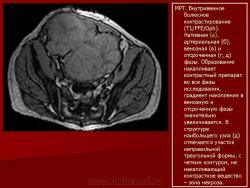

Онкология. Фибросаркома забрюшинного пространства. +

Фибросаркома забрюшинного пространства.